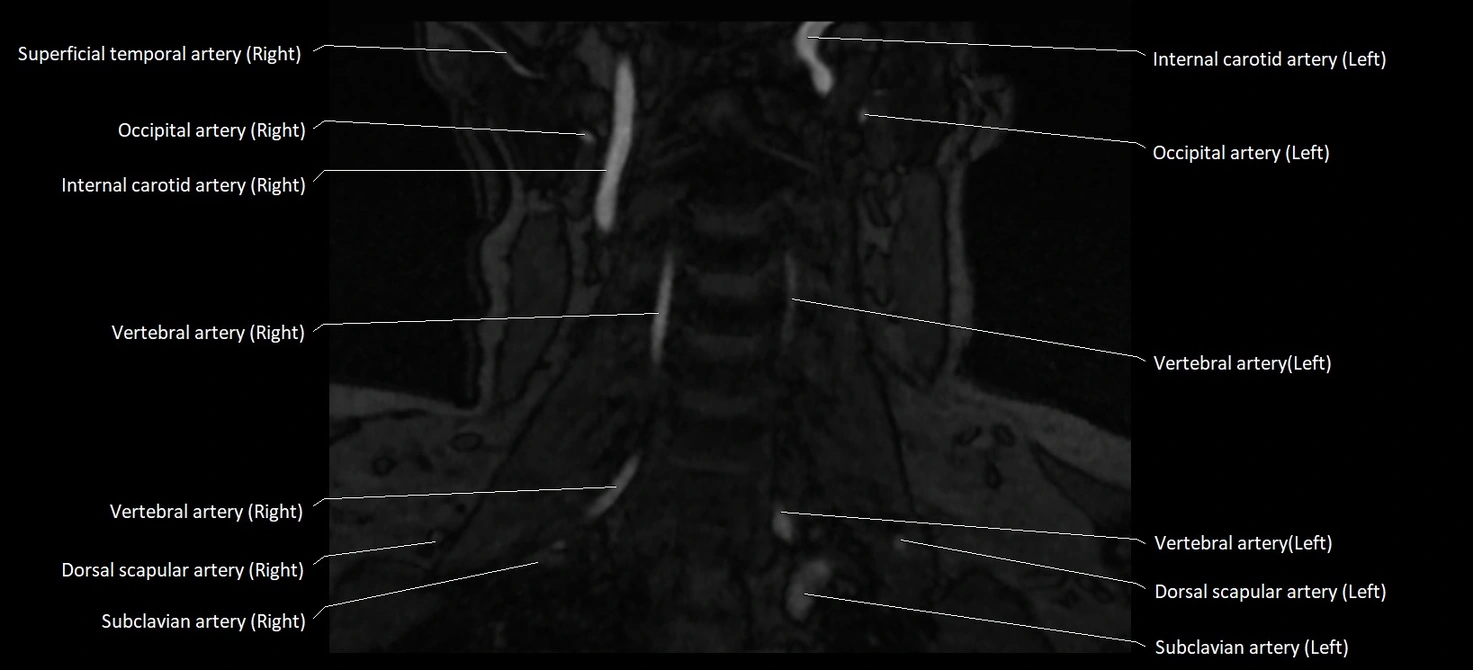

CT image

image